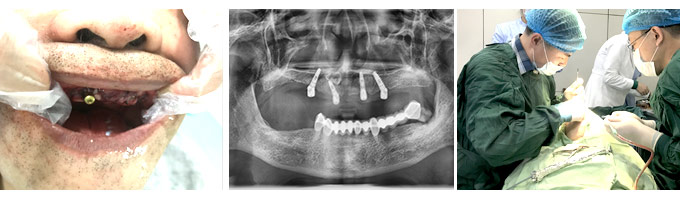

人工种植牙也就是种植牙,并不是真的种上自然牙齿,而是通过医学方式,将与人体骨质兼容性高的纯钛金属经过精密的设计,制造成类似牙根的圆柱体或其他形状,以外科小手术的方式植入缺牙区的牙槽骨内,经过 1~3 个月后,当人工牙根与牙槽骨密合后,再在人工牙根上制作烤瓷牙冠。因不具破坏性,种植牙已被口腔医学界公认为缺牙的良好修复方式。”

“人工种植牙价格包括种植体、修复基台、手术以及烤瓷牙冠价格。影响人工种植牙价格多少的因素主要有品牌、烤瓷牙冠种类、医生技术以及护理等。”